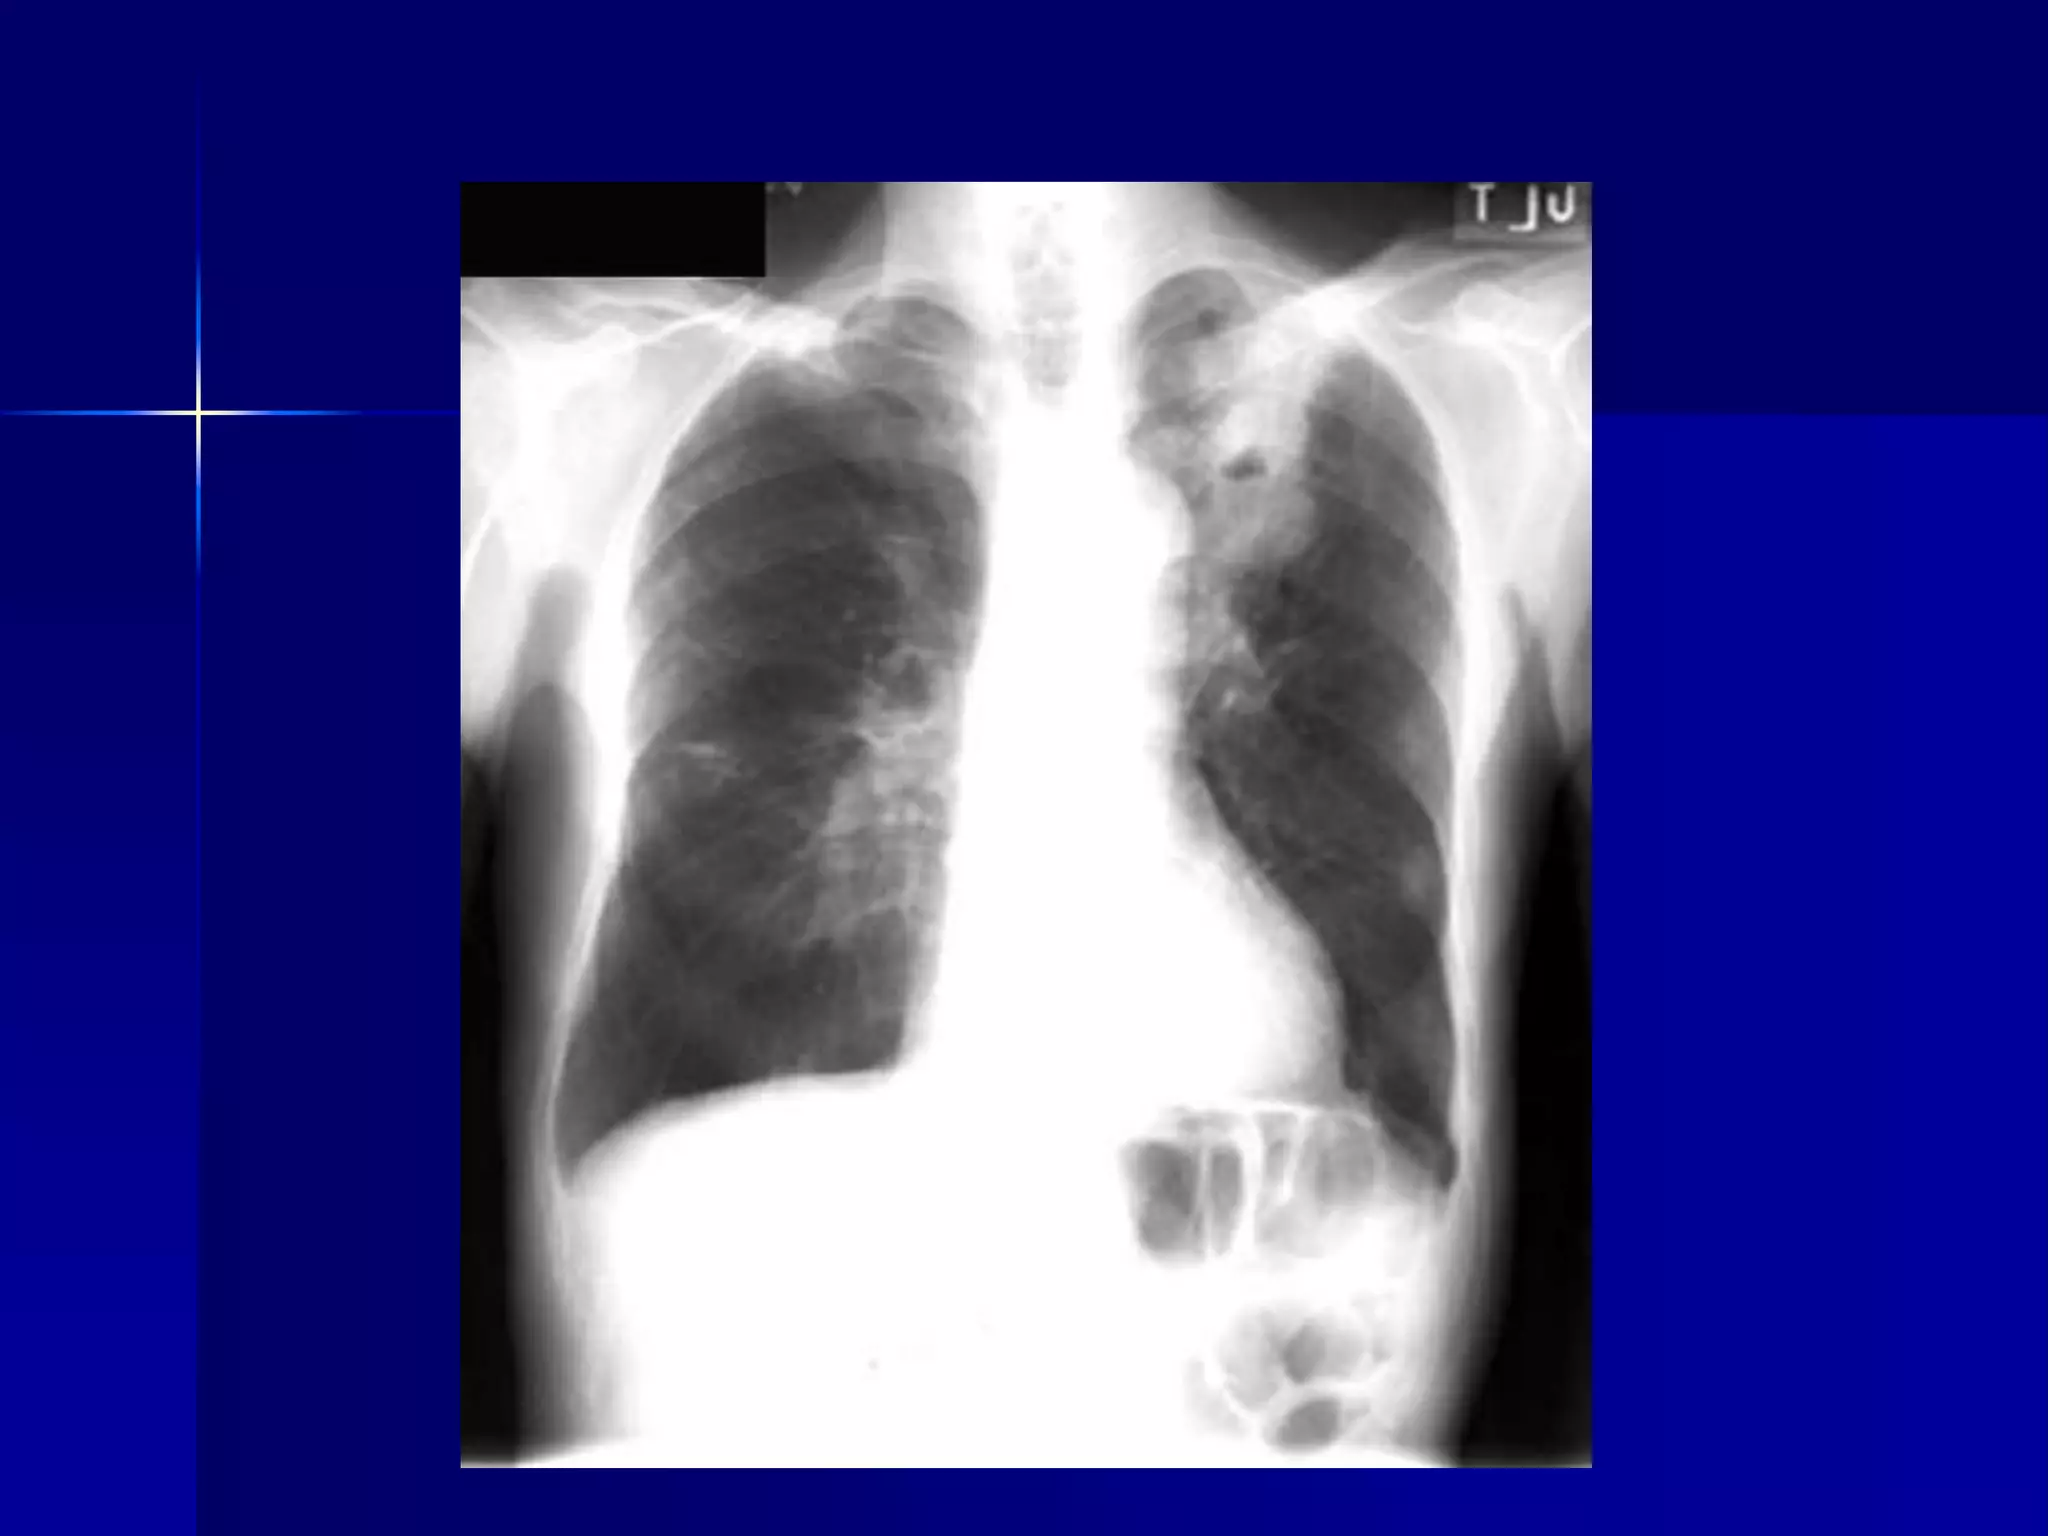

 Atelectasis Left Lower Lobe

 Inhomogeneous cardiac density

 Triangular retrocardiac density

 Left hilum pulled down

 Atelectasis LeftLower Lobe  Inhomogeneous cardiac density  Triangular retrocardiac density  Left hilum pulled down 